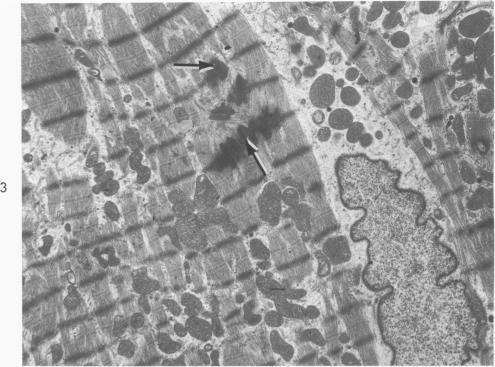

The fine structure alterations in the atrium and atrial appendage, mitral valve and papillary muscle are described in 11 matched patients with chronic rheumatic heart disease. The muscle changes consisted of loss of myofilaments and accumulation of lipid and osmiophilic dense bodies. The connective tissue stroma of the atrium and the mitral valve showed extensive deposition of collagen and elastic fibers. There were numerous foci of collagen degeneration, characterized by fraying of the collagen fibers and accumulation of homogeneous granular material at these sites. Although the muscle changes were more striking, the connective tissue alterations appear important in the evolution of the chronic disease. The extent of collagen degeneration appeared to parallel the degree of collagen formation. The muscle fiber degeneration and connective tissue alterations did not correlate with the clinical findings. At the resolution of the electron microscope, the continuing process in the rheumatic heart appears to be primarily collagen formation and degradation rather than primary degeneration of the muscle fibers. It is the balance of these processes which determine the clinical state of the patient. Acute muscle damage along with evidence of inflammation do not seem to be associated with progressive, chronic rheumatic heart disease.

在11例匹配的慢性风湿性心脏病患者中,描述了心房、心耳、二尖瓣和乳头肌的精细结构改变。肌肉变化包括肌丝丧失以及脂质和嗜锇致密小体的积聚。心房和二尖瓣的结缔组织基质显示出大量胶原纤维和弹性纤维的沉积。有许多胶原纤维变性灶,其特征为胶原纤维磨损以及在这些部位有均匀颗粒物质的积聚。虽然肌肉变化更为显著,但结缔组织改变在慢性疾病的发展过程中似乎也很重要。胶原纤维变性的程度似乎与胶原形成的程度平行。肌纤维变性和结缔组织改变与临床发现无关。在电子显微镜下观察,风湿性心脏病的持续过程似乎主要是胶原形成和降解,而非肌纤维的原发性变性。正是这些过程的平衡决定了患者的临床状态。急性肌肉损伤以及炎症证据似乎与进行性慢性风湿性心脏病无关。